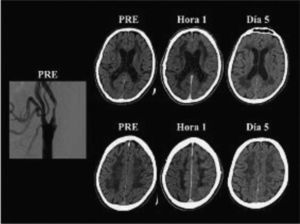

El síndrome de hiperperfusión (SHP) puede ocurrir después de la endarterectomía o de la angioplastia, con una frecuencia que varía entre el 0 y el 3% en la mayoría de las comunicaciones80–83. Puede presentarse clínicamente con cefalea difusa o con localización facial, ocular, periorbitaria o frontotemporal; vómitos, confusión, convulsiones o déficit motor. Hemodinámicamente se define como un aumento mayor del 100% en el flujo sanguíneo cerebral del hemisferio revascularizado con respecto a los valores preoperatorios84. La disfunción endotelial mediada por radicales libres y la consiguiente alteración de la autorregulación cerebral serían fenómenos centrales en la cascada fisiopatológica. La imagen característica en las neuroimágenes es el edema cerebral difuso unilateral, aunque también puede observarse en el hemisferio contralateral (fig. 5). Infrecuentemente, el SHP puede complicarse con hemorragia intracraneal (HIC). Los factores de riesgo más importantes para la HIC son la hipertensión postoperatoria, la disminución de la reserva cerebrovascular, la hiperperfusión (↑ FSC > 100%) prolongada después de la intervención, la oclusión de ACI contralateral, la escasa circulación colateral y la estenosis severa de la ACI intervenida, entre otros85. De esta manera, la medida de mayor impacto para la prevención del sangrado es el control estricto de la presión arterial postoperatoria. En un relevamiento sobre un total de 122.856 EC y 13.047 angioplastias realizadas en los Estados Unidos en el año 2005, la frecuencia de HIC fue de 0,016 y 0,15% respectivamente86; es decir, que esta complicación fue 10 veces más frecuente en las angioplastias que en las EC. En este estudio la angioplastia fue un predictor independiente de HIC (OR: 5,9; IC 95%: 3,1-11,1; p < 0,001).

Angiografía por sustracción digital y tomografía computarizada sin contraste de un paciente con síndrome de hiperperfusión post angioplastia carotídea izquierda. La figura muestra la angiografía digital de un hombre de 65 años y las tomografías computarizadas de cerebro realizadas antes (PRE), a la hora y 5 días después de una angioplastia con stent en la arteria carótida interna izquierda. Obsérvese la estenosis carotídea izquierda y el edema hemisférico izquierdo en las tomografías hechas una hora y 5 días después de la angioplastia.